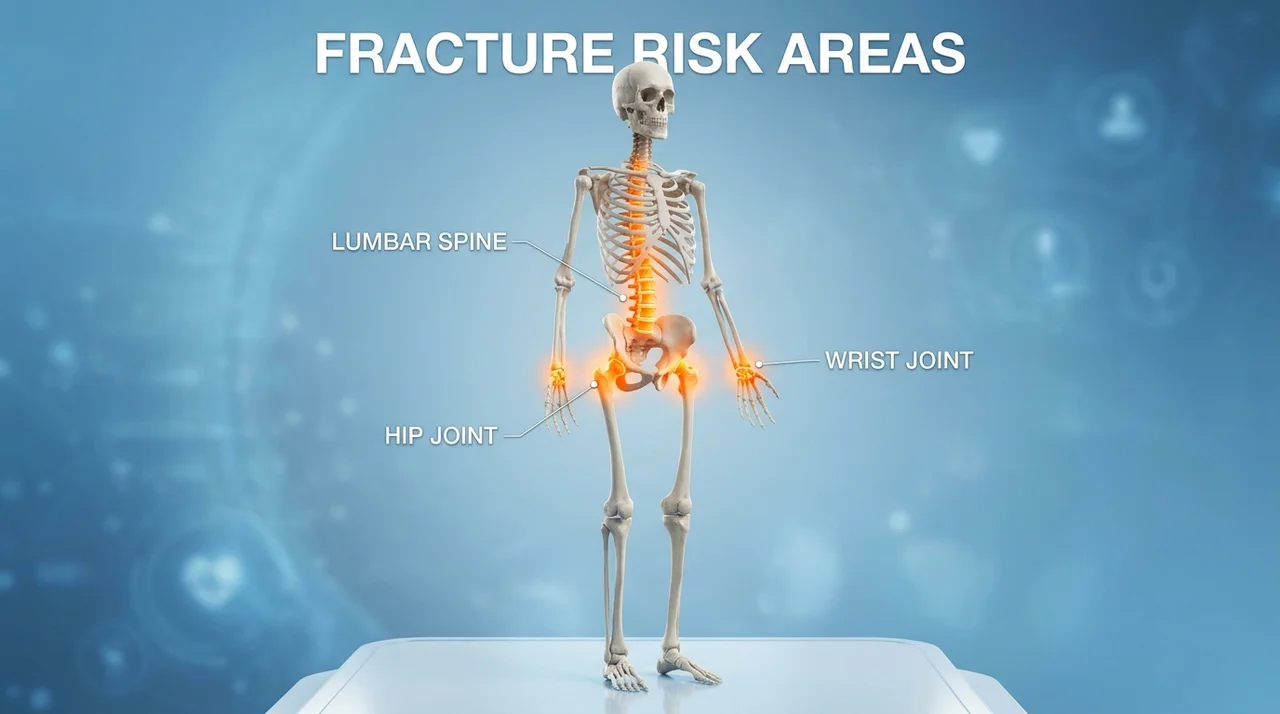

골다공증 골절의 3대 핵심 위험 부위는 고관절, 척추, 손목입니다.

한눈에 보는 골다공증 골절 위험 부위 비교

골다공증으로 인해 골절이 자주 발생하는 부위는 우리 몸의 하중을 견디거나 낙상 시 땅을 짚게 되는 곳들입니다. 각 부위별로 발생하는 연령대와 위험도가 조금씩 달라요. 아래 표를 통해 한눈에 비교해 보세요.

표에서 보시는 것처럼 고관절 골절은 생명과 직결되는 경우가 많아 가장 주의해야 합니다. 반면 척추 골절은 자신도 모르게 '꼬부랑 할머니'가 되는 원인이 되기도 하죠.